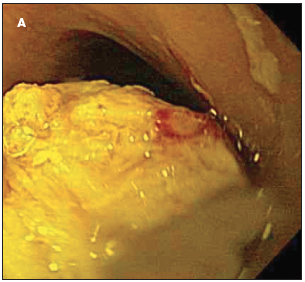

Lucia C. Fry, MD; Klaus E. Mönkemuller, MD

A 9-year-old boy was brought to the emergency department after complaining that a piece of chicken was stuck in his throat. He had dinner 3 hours earlier.